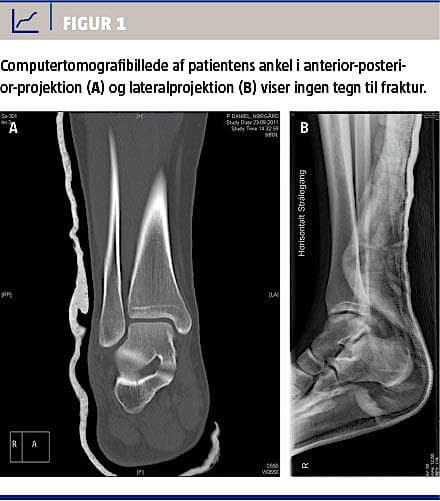

En 17-årig normalvægtig, fysisk aktiv, tidligere rask dreng blev indbragt til skadestuen efter at være hoppet op imod en anden person (chestbodding) og i nedspringet være landet forkert på højre fod. Objektivt sås en tydelig fejlstilling i ankelleddet, manglende puls i a. dorsalis pedis, forlænget kapillærrespons og manglende sensorik i tæerne. Han fik morfin og stesolid, og anklen blev reponeret; øjeblikkeligt fremkom der kapillær respons, god puls i a. dorsalis pedis og senere også normal sensibilitet i hele foden. En efterfølgende røntgenundersøgelse viste ingen tegn på fraktur, hvorfor der blev foretaget en kontrol-computertomografi (CT) også uden tegn på fraktur (Figur 1). CT’en viste lukkede epifyseskiver. Patienten blev behandlet på skadestuen og fik anlagt en Walkerbandage, som han skulle bære i seks uger, og der blev påbegyndt en tidages dicloxacillinbehandling. Patienten kom til kontrol i ambulatoriet efter en uge, hvor man fandt lettere atrofi af højre lægmuskulatur, ekstensionsdefekt på 5-10 grader og en fleksionsdefekt på 10-15 grader. Der var ingen løshed i anklen, ingen ossøs palpationsømhed, god puls i a. dorsalis pedis og normal sensibilitet. Patienten blev instrueret i restriktivt genoptræningsregime, ingen hoppen, ingen træning på blødt underlag og ingen voldsom sportstræning.